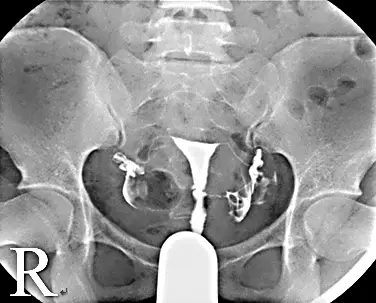

觀察本題提供的 HSG X光影像:

- 攝影技術與標示:這是一張骨盆腔前後位(AP view)的 X 光片。影像左下角帶有「R」標記,代表病患的右側位於畫面的左側。畫面最下方可看見置入子宮頸的導管(Cannula / Catheter)用於注入對比劑。

- 子宮腔(Uterine cavity):子宮腔內充滿對比劑,呈現正常的平滑倒三角形邊緣,內部無異常的充盈缺損(Filling defect),顯示子宮內部無明顯的肌瘤、息肉或沾黏。

- 輸卵管(Fallopian tubes):對比劑成功從兩側子宮角(Cornua)流入左、右雙側的輸卵管。兩側輸卵管管徑細長正常,無呈現香腸狀或囊袋狀的擴張(即無輸卵管積水 Hydrosalpinx 的跡象)。

- 腹膜腔溢出(Peritoneal spillage):在畫面左右兩側(即病患雙側)的輸卵管遠端外側,皆可觀察到對比劑呈現不規則、煙霧狀或抹塗狀的散布(Smudging pattern)。